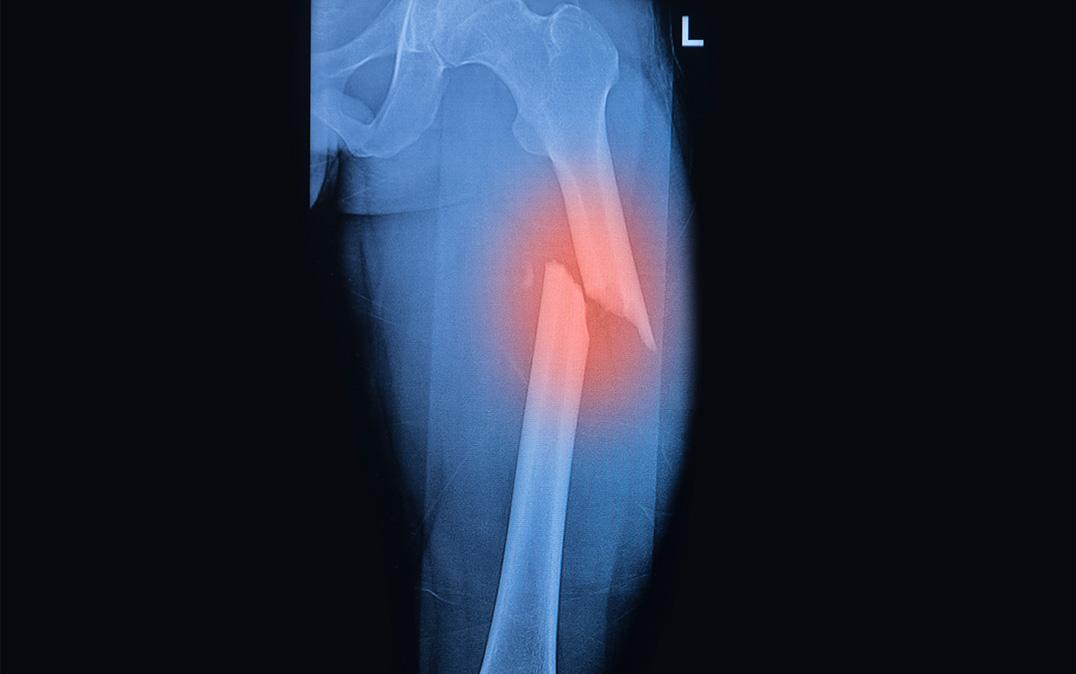

このマウスからCD73陽性MSCsとCD73陰性MSCsを単離し、性質を比較したところ、CD73陽性MSCsは、生体外において高い増殖能と骨・軟骨細胞への分化能を持つことが分かりました。また、マウス大腿部に骨折を作製し、骨修復におけるCD73陽性MSCsの動態解析より、CD73陽性MSCsは骨折部位に遊走し、骨芽細胞や軟骨細胞に分化し、積極的に組織修復に関わっていることが判明しました。一方、CD73陽性血管内皮細胞は、骨修復中期に骨折部位に観察され、周囲には造血幹前駆細胞が集積し、ニッチの再構築に働いていました。以上のことから、CD73発現細胞はニッチの再構築に重要な役割を示すことが明らかとなりました。